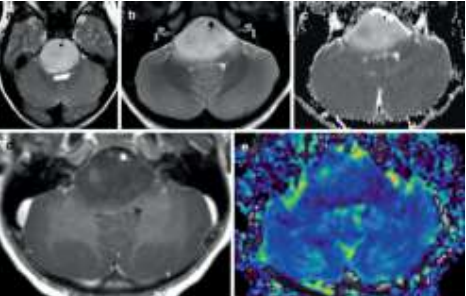

Criança de 7 anos, com histórico recente de diplopia por alteração da mobilidade ocular extrínseca foi encaminhada para realização de ressonância nuclear magnética de crânio em contexto de investigação diagnóstica, apresentando a seguinte imagem:

Baseado nas características epidemiológicas e os achados de seu exame de imagem, e considerando a classificação dos tumores do sistema nervoso central da OMS (2021), assinale a alternativa correta.